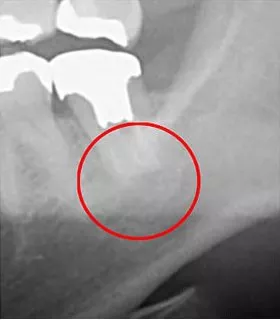

下の画像を見てみていただけますか?

他の治療ケースですが、左がレントゲンで、右がCTで撮影した画像です。

丸がついている部分が「問題部位」です。

3次元の方は「黒い影」が確実に見えます。2次元ではほとんど確認できません。

もしもレントゲンでの診査診断なら、問題なしという結論になってしまいます。

歯科治療においては、それほど「見える」ということは重要なのです。